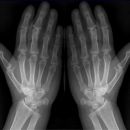

Scaphoid-Quartett

Dringender Verdacht auf Scaphoidfraktur (2) bei zweifelhaften Befund in den Standardprojektionen.Notwendigkeit fraglich, da bei klinischen Verdacht und zweifelhaften Röntgenbefund in den Standardaufnahmen des Handgelenks ohnehin die Ruhigstellung indiziert ist, so dass sich eine weiterführende Diagnostik zunächst erübrigt. Ist auch die Kontrolluntersuchung nicht eindeutig, so sind CT oder Szintigraphie in ihrer Aussage zuverlässiger als die Spezialprojektionen.

Scaphoidfrakturen: 70% der Frakturen der Handwurzel sind Scaphoidfrakturen. 2/3 sind im mittleren Drittel. Meist Querfrakturen.

Dehizenz > 1mm -> instabil -> Gefahr Pseudarthrose.

Cave: Begleitverletzungen: Proc. syloideus radii, Lunatum, Capitatum, SL-Dissoziation, perilunäre Dissoziaton, DeQuervain Luxationsfraktur.